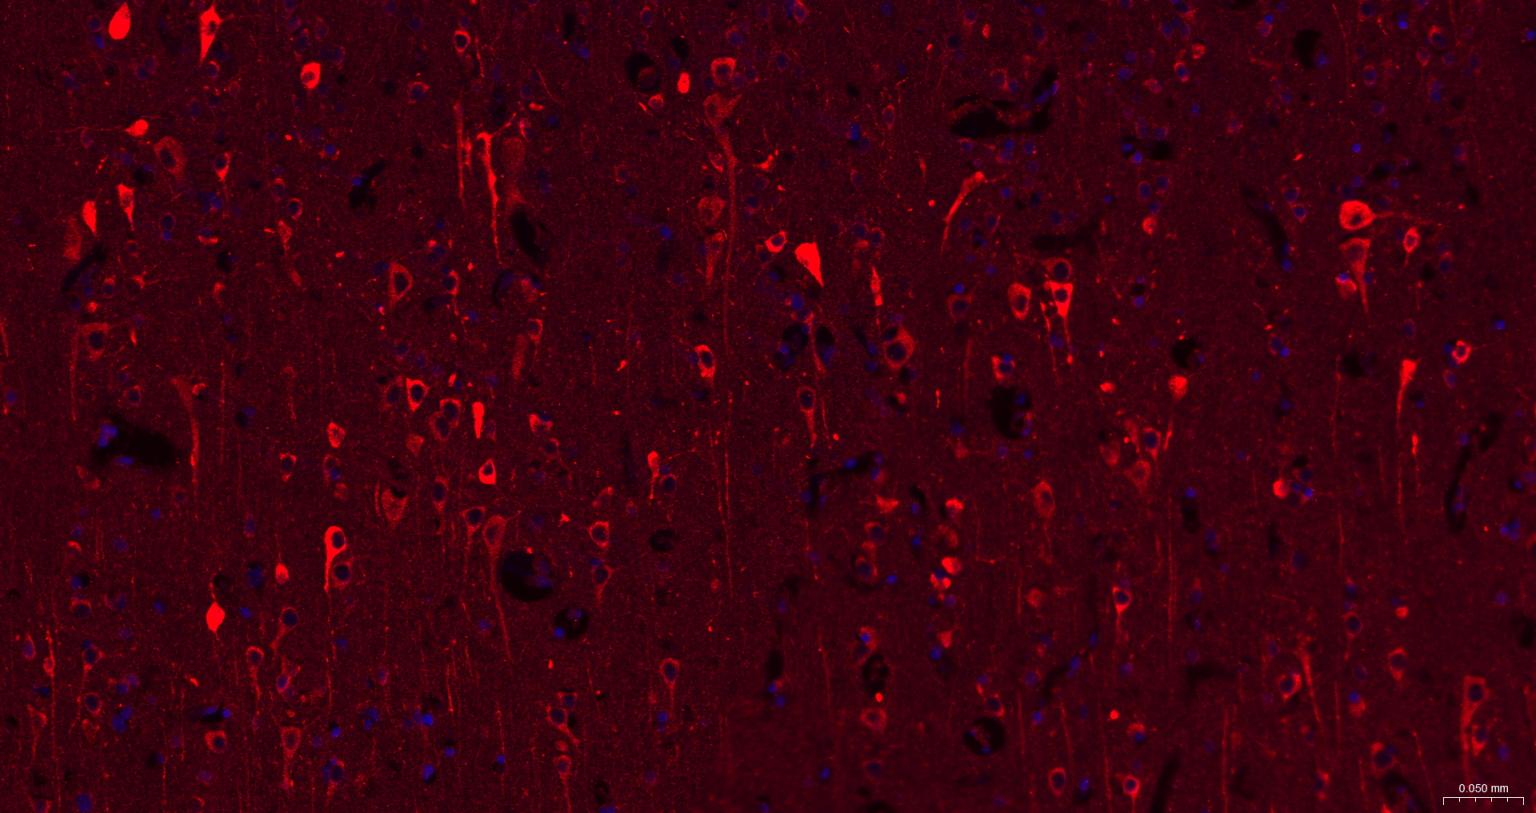

Paraformaldehyde-fixed, paraffin embedded human brain; Antigen retrieval by boiling in sodium citrate buffer (pH6.0) for 15 min; The section was incubated with Leptin Receptor Monoclonal Antibody, Unconjugated (bsm-61055R) at 1:200 overnight at 4°C. Followed by conjugated Goat Anti-Ratbbit IgG antibody (red, bs-0295G-BF594), DAPI (blue, C02-04002) was used to stain the cell nuclei.